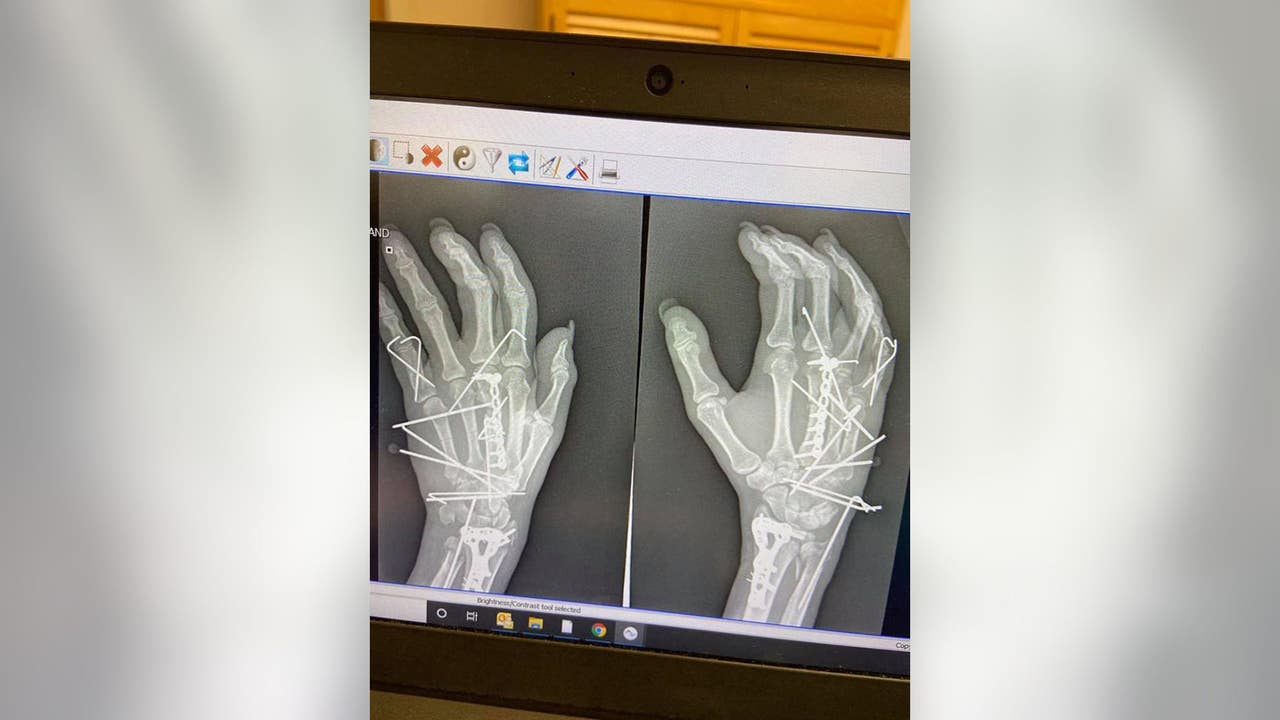

"I actually remember quite a bit," Anema said while speaking with FOX News. "My hand blew basically in half. All I saw was my wrist bone and I knew something was wrong."

Anema's family called 911 and she was rushed to the hospital. She said the injury was so bad that doctors spoke with her husband and considered amputation. Fortunately, they were able to save the hand, along with all of the fingers.

"Most people don’t realize how severe the injury really is until they see the pics," Anema said, adding that she wants to spread awareness by sharing her story.

Anema said that since the accident, about 70% of use of her hand has returned. She credits the "wonderful" team of doctors she’s worked with for helping her to recovery.